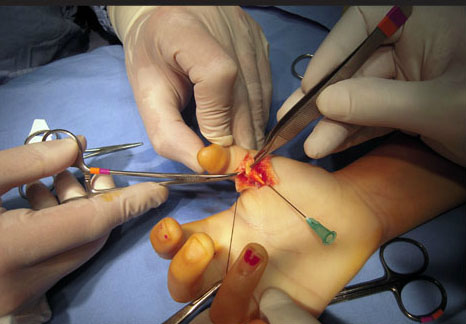

CIRUGIA DE MANO

Y MIEMBRO

SUPERIOR

Casos de exito

Cirugías, operaciones y tratamientos.

ESPECIALISTA EN ORTOPEDIA Y

TRAUMOTOLOGIA,CIRUGIA DE MANO

Y MIEMBRO SUPERIOR